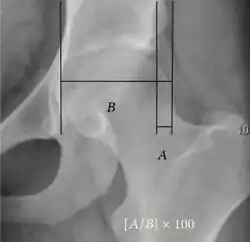

Other measurements in adult hip.[notes 1][3]

Measurement Image Target Normal value

Acetabular depth ratio Deepness of acetabulum.

• The width is measured between the inferior margin of the teardrop and the lateral rim of the acetabulum.[11]

• The depth is measured perpendicularly from the midpoint of the width line.[11]

>250

• Less indicates a dysplastic hip